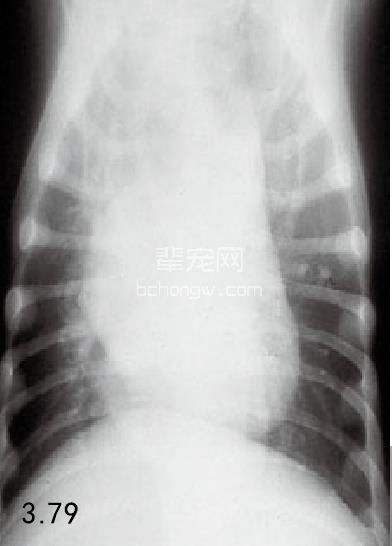

诊断 通过病史和胸腔常规X线片可以诊断 (图3.77~图3.80),但如果需要确定特殊的病 因,则需要进行额外的试验(表3.7)。如果不能 确诊可以做食管X线片和食管镜试验,但通常没有 这个必要(图3.81和图3.82)。德国牧羊犬、大丹 犬、爱尔兰赛特犬、小型雪纳瑞犬和硬毛 易患 先天性巨食管症。犬胃扩张-扭转综合征时,也 可能暂时性继发巨食管症。

图3.77 16周龄德国牧羊犬具有“玩耍时发生呕吐”史,胸腔X线检查发现为巨食管症。

图3.78和图3.79 在图3.77中所述幼犬的食道造影X线片可见食管的巨大扩张。